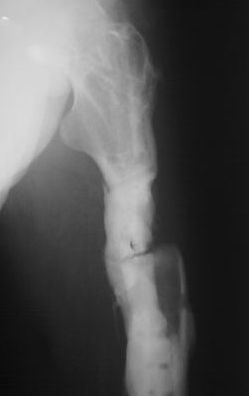

Рефрактура бедренной кости |

Подробности из анамнеза: в 2007 году пациенту выполнена операция остеосинтез бедренной кости по поводу многооскольчатого перелома с применением пластинки с ограниченным контактом (имплантов с угловой стабильностью и блокируемых гвоздей на момент операции в наличии не было - это, чтобы не обсуждать лишние вопросы). Через 6,5 месяцев после остеосинтеза развился остеомиелит в верхней трети диафиза бедренной кости с образованием секвестра размерами 55х30х25 мм. В 2008 году (через 8 месяцев после остеосинтеза) выполнена вторая операция - удаление металлоконструкции и секвестрэктомия. При удалении пластинки и ревизии ложа секвестра, костная мозоль на сросшемся участке состоятельна. было принято решение заполнить секвестральную полость мышечным лоскутом. В послеоперационном периоде нагрузка на конечность была исключена 2,5 месяца, дополнительная фиксация индивидуальным брейсом. Свищи зажили, обострения остемиелита купировано. Пациент приступил к профессиональной деятельности (автослесарь). В конце ноября при уборке снега произвел резкую опорную нагрузку на конечность, после чего появились умеренные боли нарастающие в течение месяца. В настоящее время госптализирован для оперативного лечения по поводу рефрактуры на уровне верхней трети бедренной кости. Планируется остеосинтез аппаратом Илизарова с стержневой модификации (без обширного вмешательства в зоне перелома)и как вариант тунеллизации через зону перелома с возможным введением в каналы "КоллапАнна", "Сhronos" и.т.п. Также были предложены варианты пластинками с угловой стабильностью, блокируемый остеосинтез гвоздями. Движения в коленном суставе до повторного перелома (сгибание 90 градусов, разгибание 180). Пациент пониженного питания. Какие есть мнения по решению данного случая, может кто-то сталкивался с подобными вариантами развития событий. Всем заранее благодарен за Ваше время. Михаил.